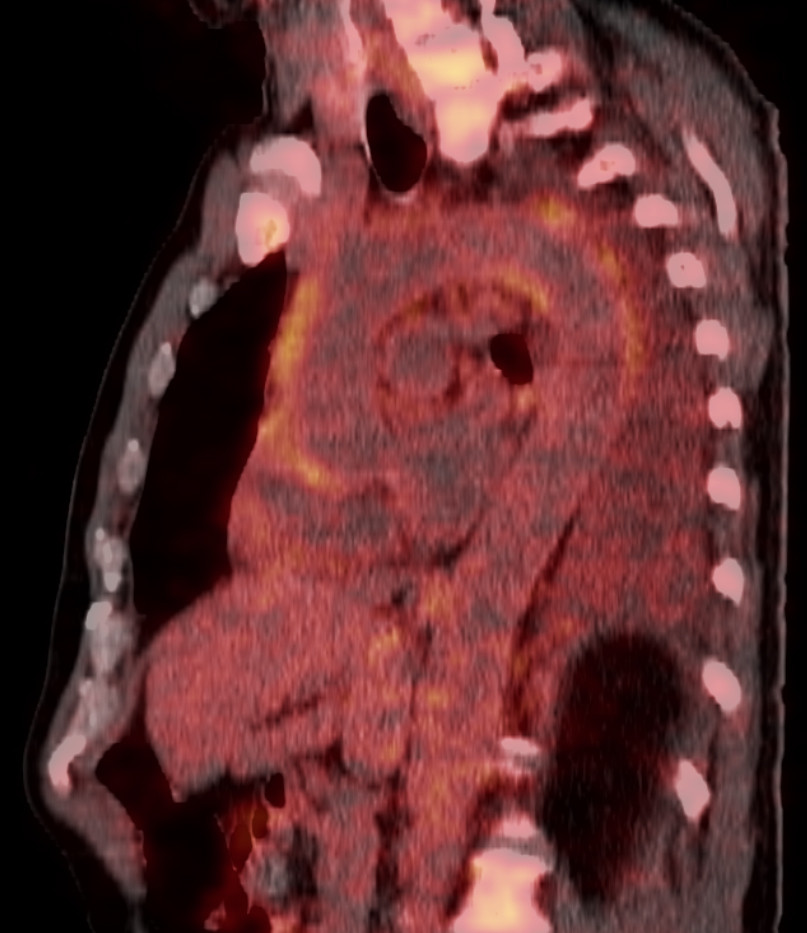

PET-CT scanning with 18F-fluorodeoxyglucose (18F-FDG) performed on admission showed increased uptake of 18F-fluorodeoxyglucose in the thoracic aorta, aortic arch branches and pericardium (Figure 1).

There was also increased uptake of 18F-fluorodeoxyglucose in bone marrow and lymph nodes, which were considered to be reactive changes. In addition, an infiltrate in the lower lobe of the left lung and pleural effusion were also found (Figure 2).